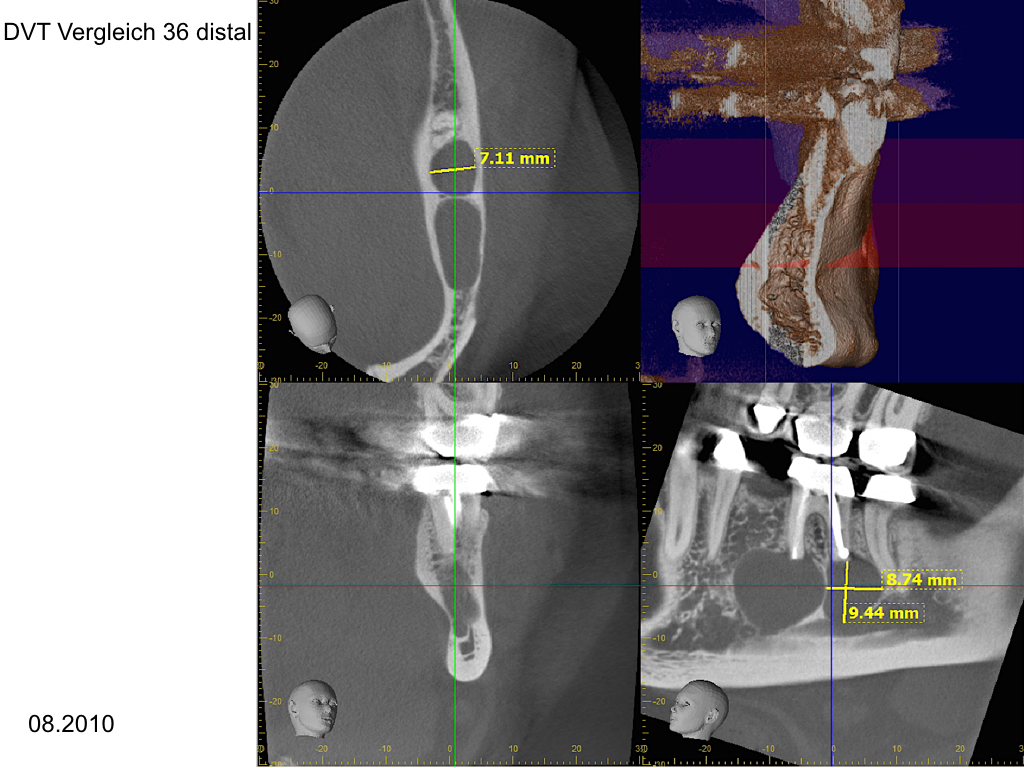

WS_Zy UK.006

Eine Fallvorstellung (2)